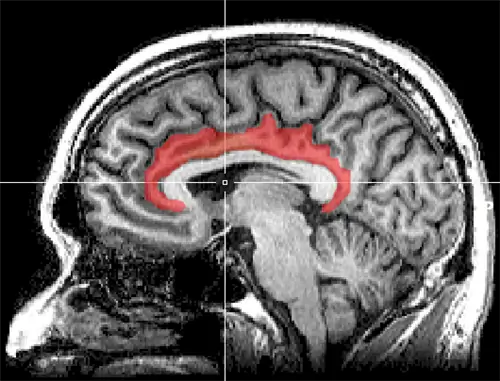

Процедура, в которой используются лазеры, называется передней цингулотомией и на данный момент одобрена только для лечения обсессивно-компульсивного расстройства (ОКР). Хирург просверливает крошечное отверстие в черепе пациента, затем вводит в мозг крошечное лезвие, чтобы прорезать путь к передней поясной коре, части мозга, которая связывает эмоции с физическими задачами. Как только инструменты хирурга достигают нужного скопления нейронов, они запускают лазер, выжигая поражения в небольшой конкретной области серого вещества. Лазер, по сути, расплавляет часть мозга, что наносит меньше вреда, чем его взламывание, как это делается при традиционной лоботомии.